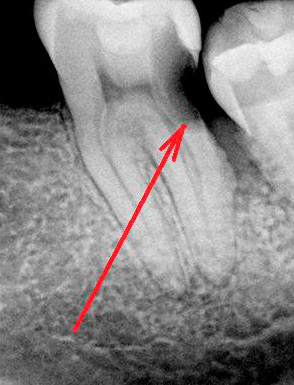

E in questa immagine c'è un roentgenogram di un dente con carie nascosta in una fase piuttosto avanzata di sviluppo. Si può vedere che l'area interessata dalla carie si è avvicinata al canale con il nervo:

Un tipico caso clinico: in un paziente, tra due denti affetti da carie, ce n'è uno, apparentemente sano, senza danni visibili. La logica suggerisce che se sono colpiti due denti, è probabile che siano interessati dalla carie e che si trovino tra di loro. Assegno una radiografia al paziente per verificare l'integrità dei tessuti interni. Sulla radiografia si vede una carie ben sviluppata vicino alla parete posteriore del dente. La sconfitta non aveva ancora raggiunto la polpa, ma penetrò in profondità nella dentina. In questa situazione, è stato sufficiente pulire l'area danneggiata e sigillare.

La foto sotto mostra la carie nascosta con un'ampia area della lesione (radiografia), una parte significativa della corona dentale è coperta da patologia: